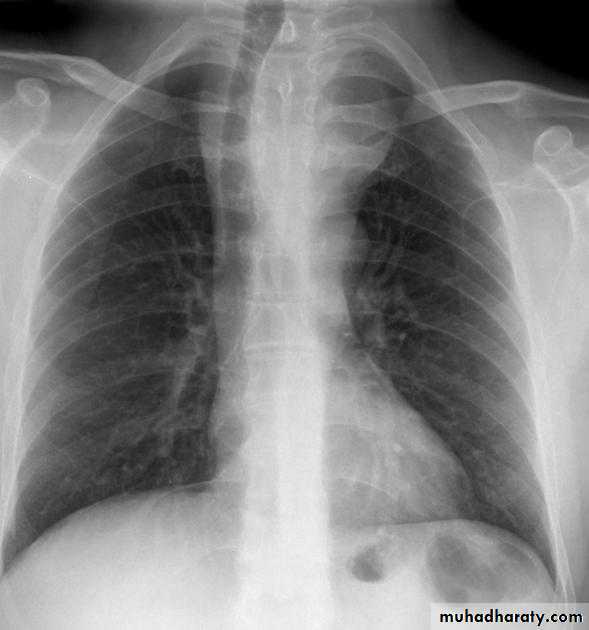

Normal chest XR PA & lateral view

Look carefully on both diaphragmatic cruse costo & cardio phrenic angles

Don't forget to use rib in asses lung Zones

8.normal chest XR PA & lat. view

9.normal radiologic anatomy of the chest

10.normal chest anatomy